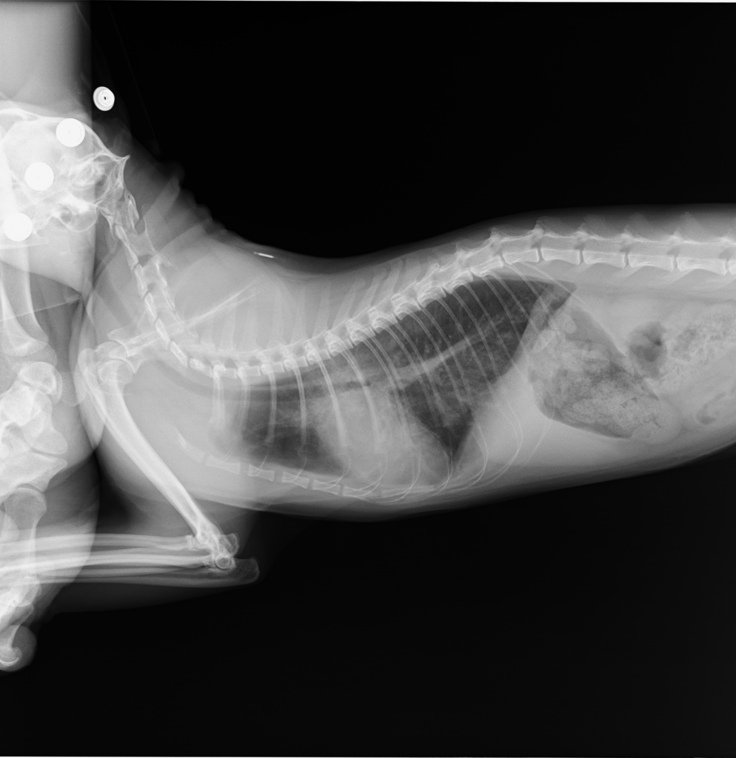

2021年9月

再び、咳の症状が出てきてきたので病院へ行きました。

その時のレントゲン写真です。

2019年のものと比べると、明らかに心臓の上部が肥大し、

位置も体の中央によっています。

ここで肥大型心筋症と診断されました。

そして、治ったと思っていた気管支炎も、まだ完治しておらず

肺がまだ若干白いままです。